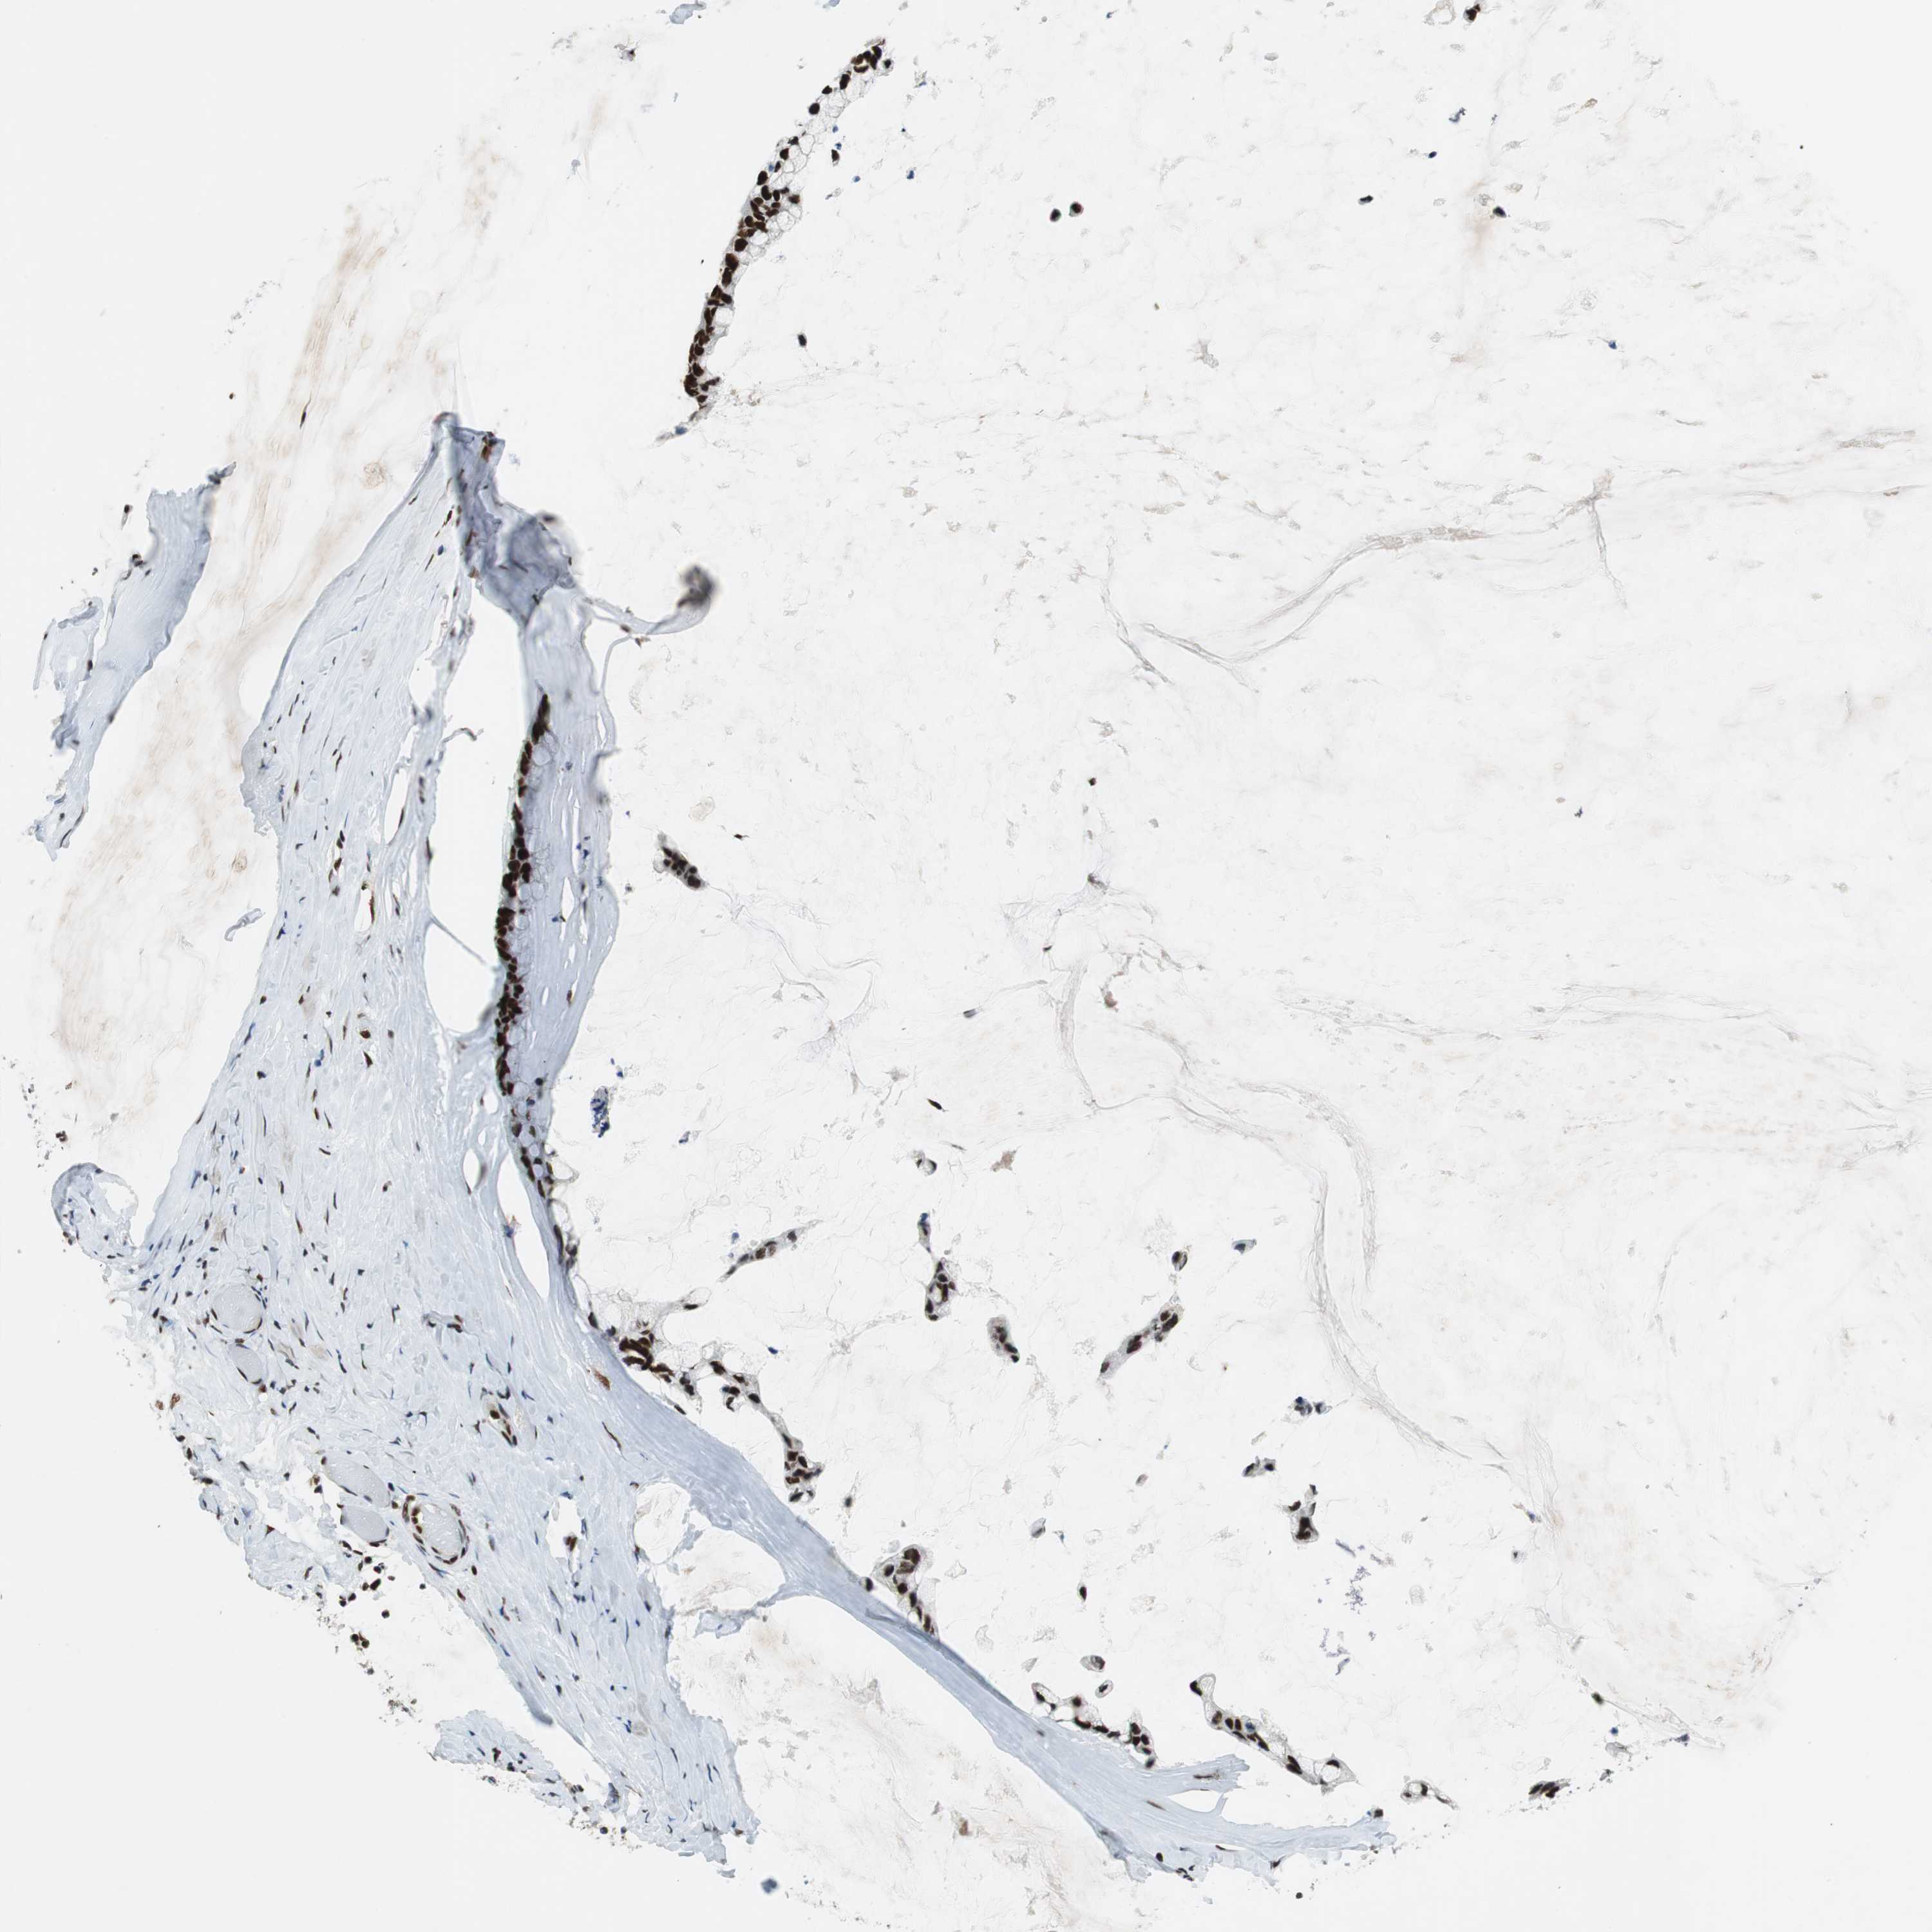

OVARIAN CANCER - Protein expressioni

A mouse-over function shows sample information and annotation data. Click on an image to view it in a full screen mode. Samples can be filtered based on level of antibody staining by selecting one or several of the following categories: high, medium, low and not detected. The assay and annotation is described here.

Note that samples used for immunohistochemistry by the Human Protein Atlas do not correspond to samples in the TCGA dataset.

Antibody stainingi

Antibody staining in the annotated cell types in the current human tissue is reported as not detected, low, medium, or high, based on conventional immunohistochemistry profiling in selected tissues. This score is based on the combination of the staining intensity and fraction of stained cells.

Each image is clickable and will lead to virtual microscopy that enables deeper exploration of all samples and also displays staining intensity scores, fraction scores and subcellular localization as well as patient and tissue information for each sample.

Antibody HPA035174

Antibody CAB005167